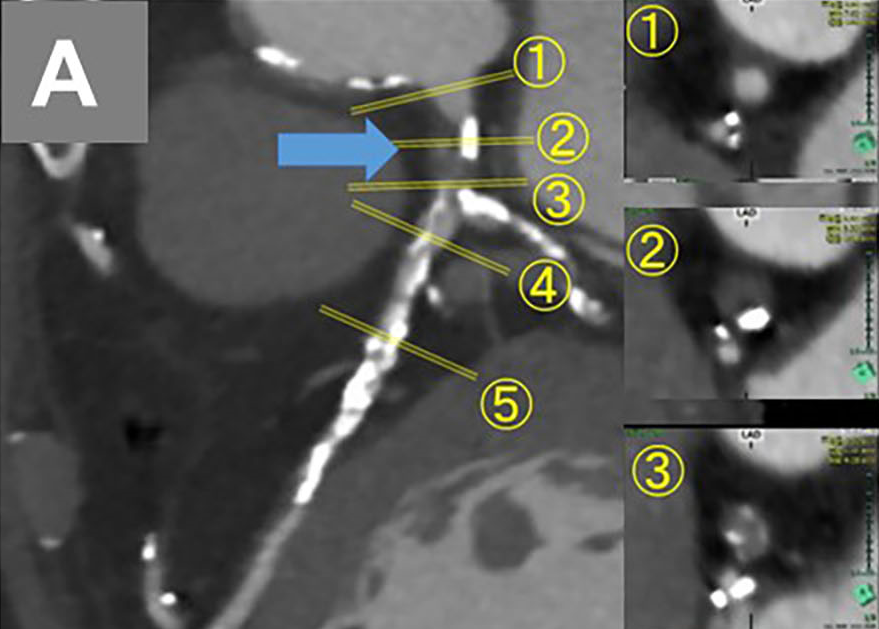

An 83-year-old man who had undergone coronary aorta bypass graft surgery 25 years ago required treatment for new-onset worsening angina. Coronary computed tomography angiography (CCTA) showed total occlusion of the left main coronary artery (LM), proximal obtuse marginal (OM) branch and proximal right coronary artery (RCA), a tight, calcified lesion in the proximal left anterior descending artery (LAD) (Figure A), patent bypasses of the left internal thoracic artery (LITA) to the LAD and the right internal thoracic artery (RITA) to the OM branch, and occlusion of the saphenous vein graft (SVG) from the aorta to the right coronary artery (RCA). Coronary angiography revealed total occlusion of the RCA and LM in their ostia (Figure B-a, b), retrograde perfusion to the proximal LAD and left circumflex artery (LCX), distal RCA by LITA-LAD graft (Figure B-c; Video 1), and limited perfusion of the OM branch by the RITA-OM branch graft (Figure B-d; Video 2). The symptom derived from a large myocardial ischemia in the postero-lateral and inferior areas.

Since CCTA indicated a blunt-type LM chronic total occlusion (CTO) in the straight route that was composed of fibrous tissue and connected to distal bifurcation (Figure A), percutaneous coronary intervention (PCI) for LM-CTO was performed with contralateral injection from the LITA-LAD. A 7-French AL2.0 SH guide catheter (Heartrail II, Terumo) was engaged in the LM and a tapered stiff guidewire (X-treme XTA, Asahi Intec) penetrated the CTO lesion and crossed to the LCX (Video 3). Intravascular ultrasound confirmed the guidewire’s penetration of the true lumen. (Figure C; Video 4). A 3.5 x 22-mm zotarolimus-eluting stent (Resolute Onyx, Medtronic) was implanted from the LM ostium to the proximal LCX (Figure D-a). Proximal optimization with a 4.0-mm balloon (Figure D-b), and final kissing balloon inflation with 3.5 and 2.5-mm balloons (Figure D-c) followed. Complete antegrade flow from the LM to LCX and good collateral flow into the distal RCA was achieved (Figure E-a, b; Videos 5 and 6). The proximal to middle LAD lesions were left untouched due to sufficient flow from the LITA-LAD graft (Figure E-c). Informed consent was obtained from the patient prior to all procedures.